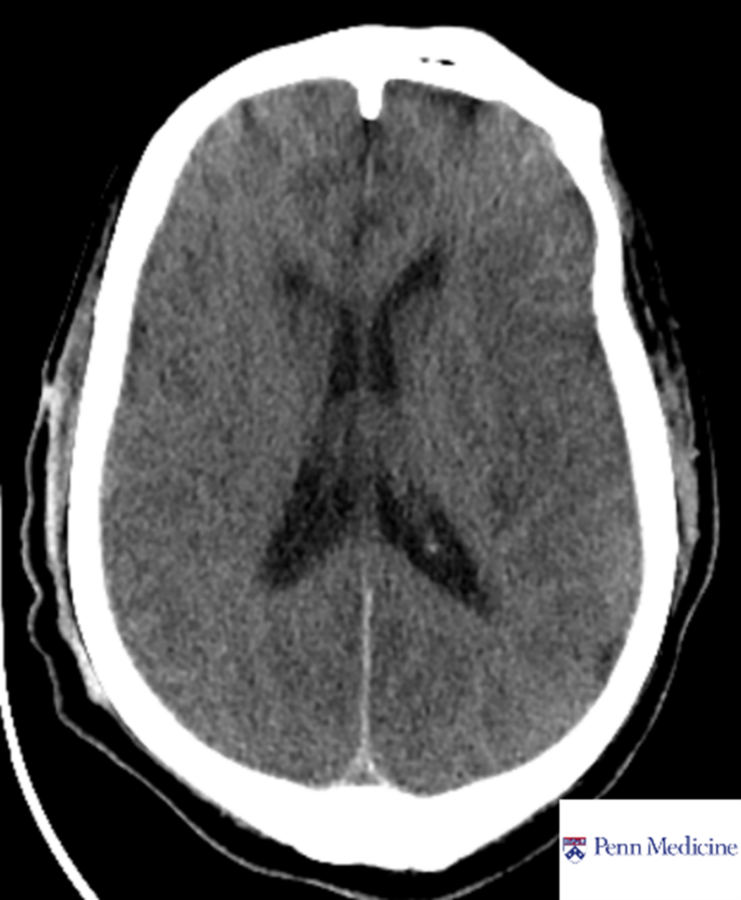

60-year-old woman with weight loss, fevers, confusion

A 60-year-old woman with history of treated pulmonary adenocarcinoma and renal and pancreas transplantation on chronic immunosuppression presents with progressive weight loss, fevers, and confusion.

Published Date: February 26, 2026

Tags:

Brain

,

CT

MRI

Neuroradiology